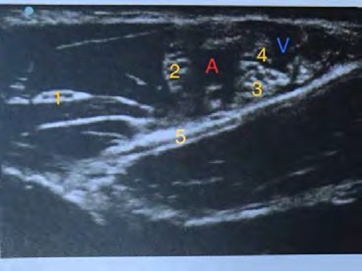

image

Décrivez les différents éléments anatomiques observés lors d'un bloc axillaire échoguidé (numérotés de 1 à 5).